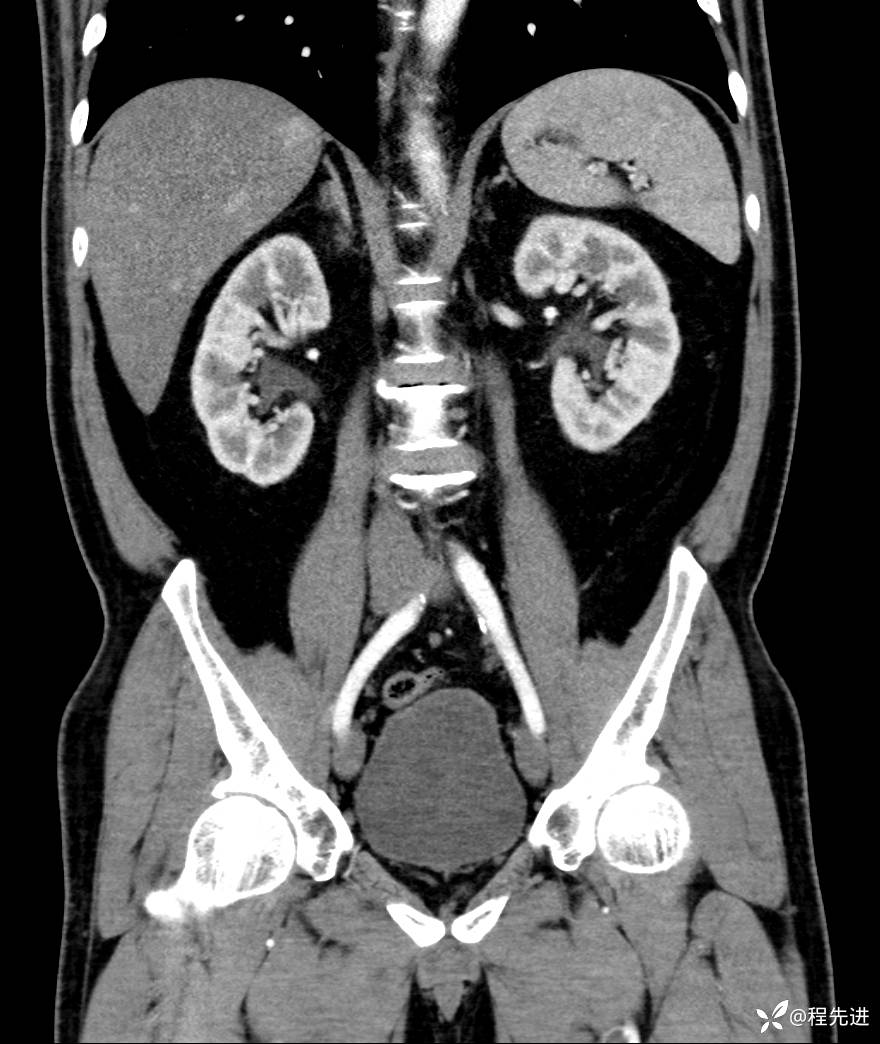

【腹盆】特别精彩病例|发现腹膜后肿物1月余

主诉:发现腹膜后肿物1月余

现病史:患者1月余前查体,行超声检查提示:后腹膜囊实性肿块;慢性胆囊炎伴胆囊内结石;无腹痛腹胀,不伴腹泻发热等;偶感腰背部酸痛。

CT平扫+增强: